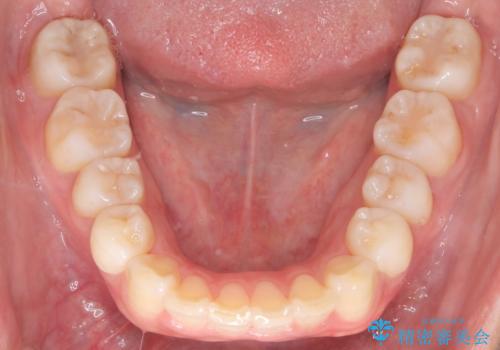

下の歯並びに対して、上の歯が全体的に前方に位置している状態でした。

上の歯の前から4番目の歯を2本抜歯して、そのスペースに前歯を移動させて、前歯を引っ込める計画としました。

抜歯をすることでしっかり前歯を後方に移動させて、引っ込めることができました。